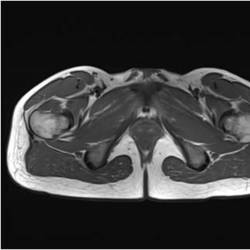

Gallery of Unlabled Radiographs from Lecture (Dr. French) - 2020

Click a thumbnail to enter the gallery display. Click the file name link at the bottom left of the gallery display to view the image at high resolution.